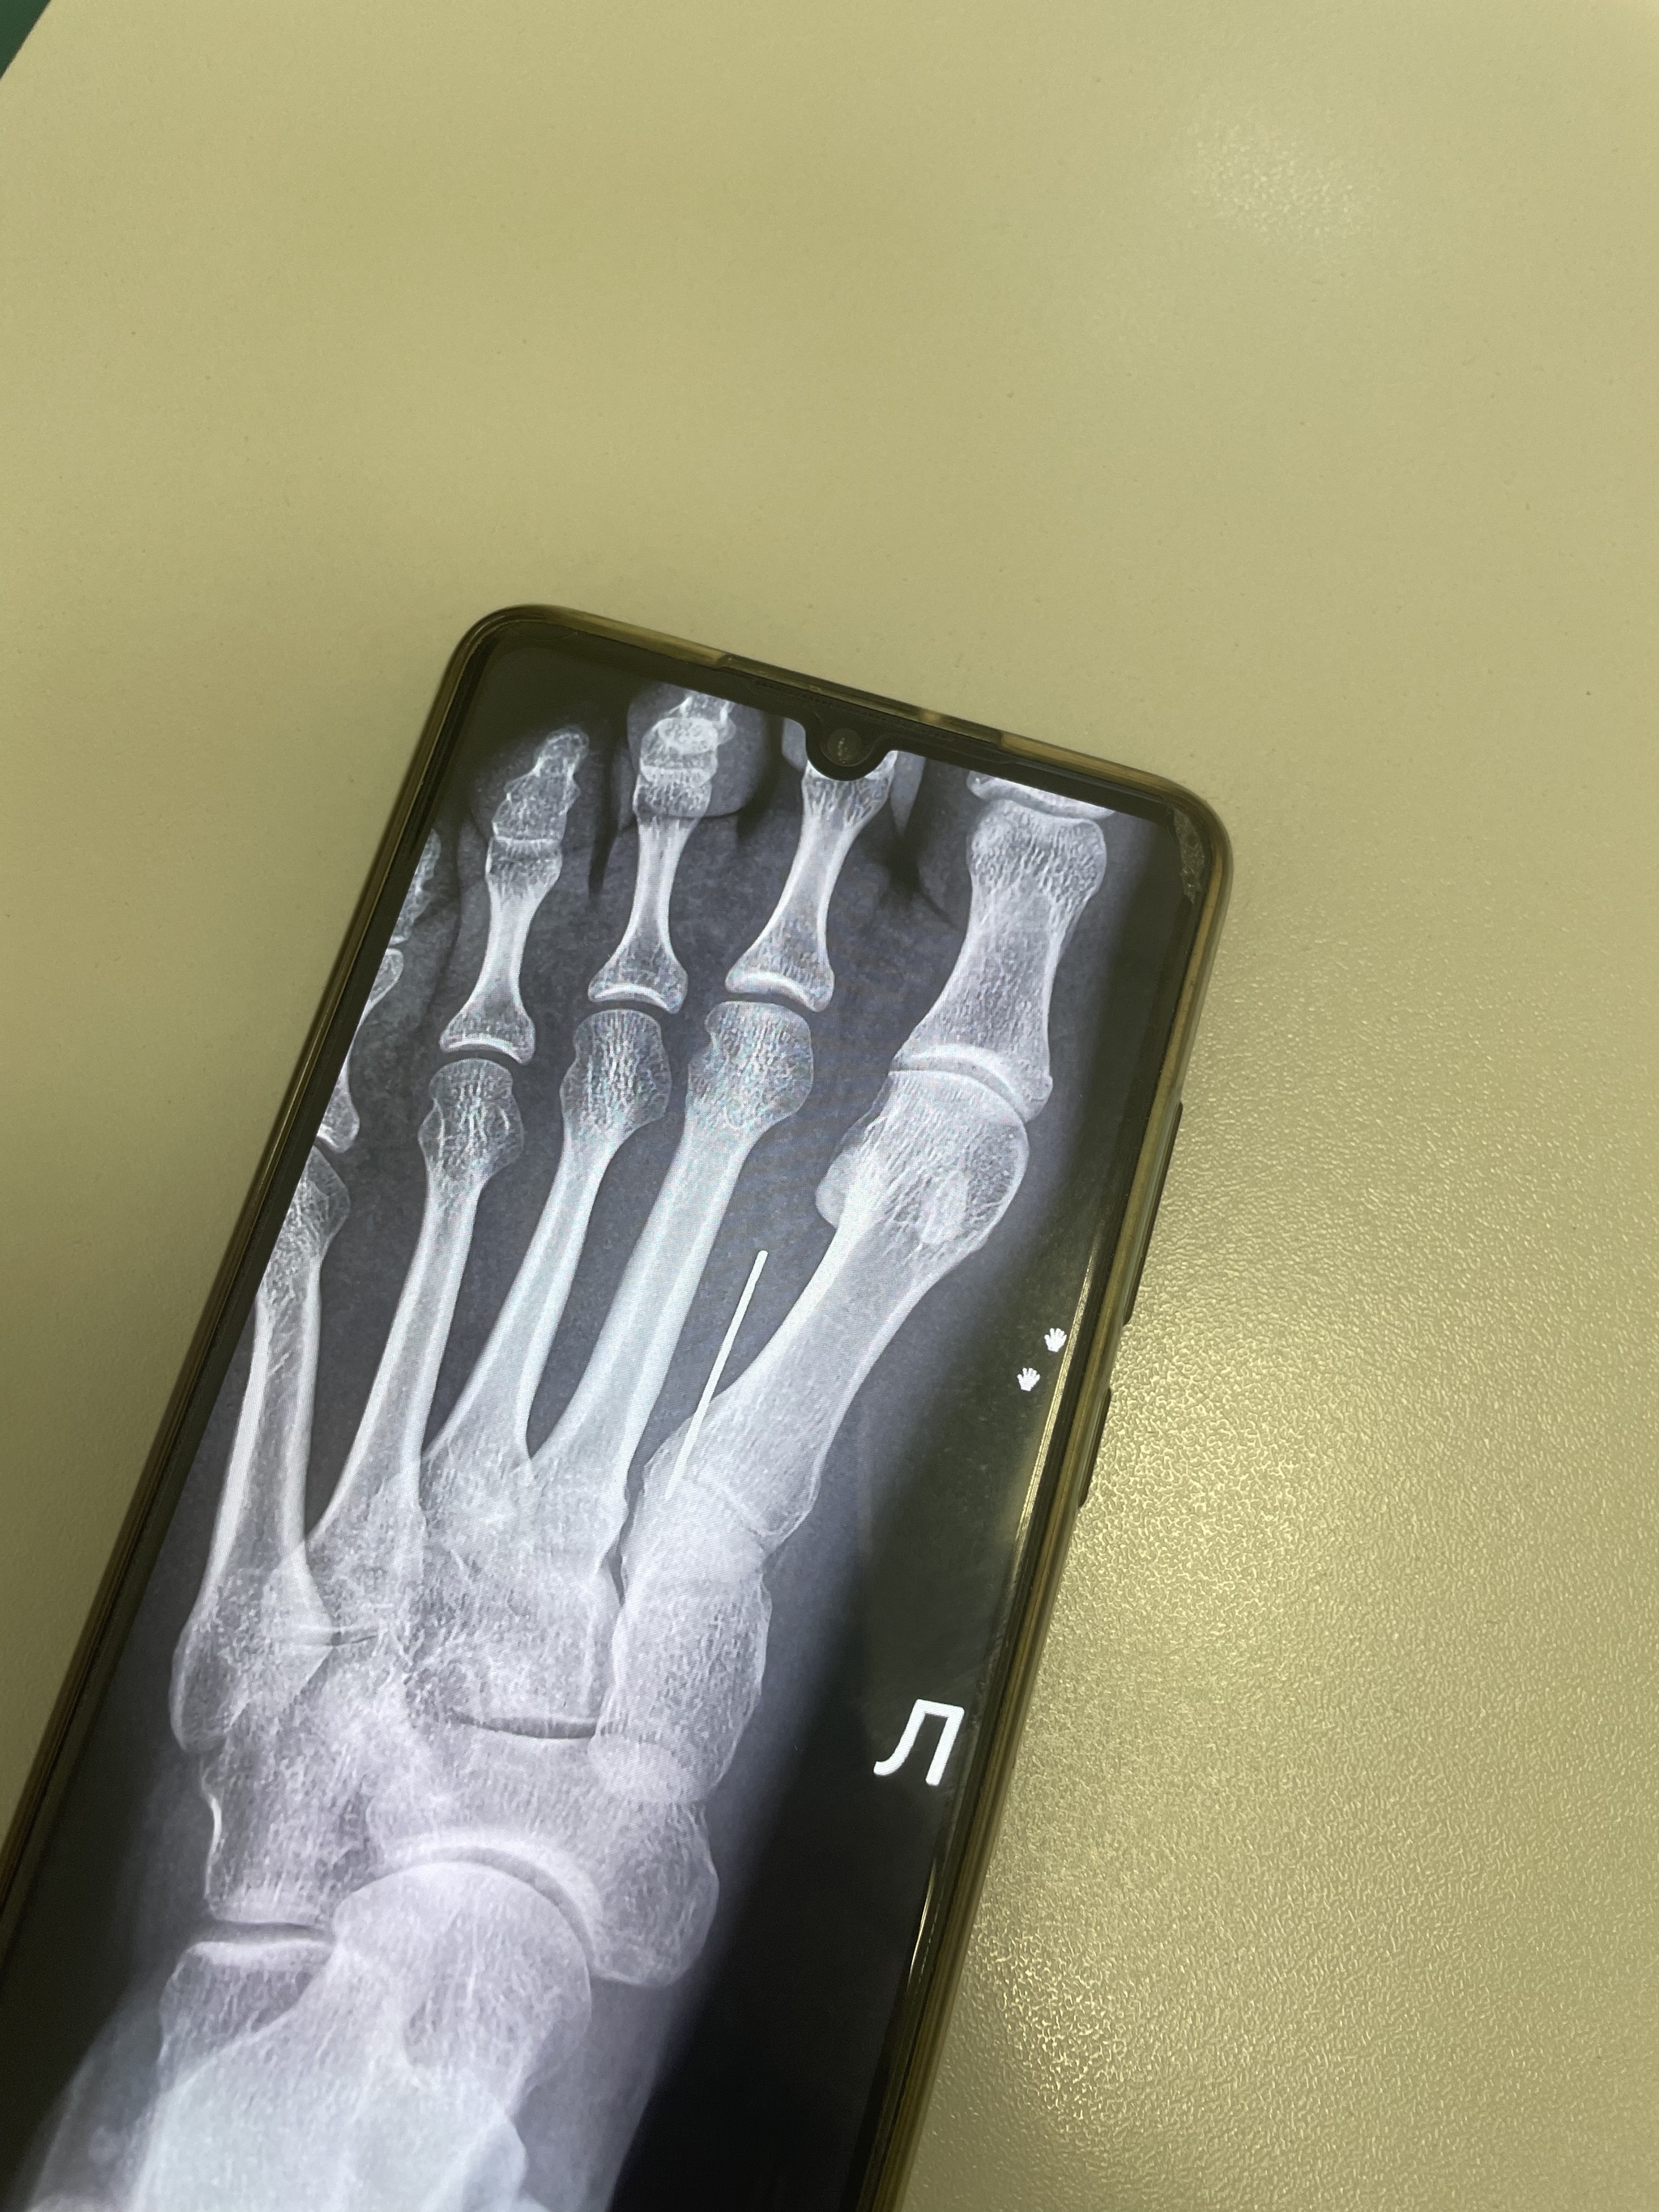

На следующий день к ортопеду. Тот показывает мне заключение рентгена, где написано, что в ноге инородный объект. Я пожимаю плечами и говорю, что понятия не имею. Врач уходит за снимком и возвращаясь, показывает мне на телефоне мою же ногу с длиннющей иглой, всаженной горизонтально!!! Я бледнею, врач говорит, что игле уже не меньше 10 лет, сформировалась защитная капсула вокруг.

Итог, назначили плановую операцию, иглу будут вынимать под местной анестезией. Я пока что нервничаю, неприятно осознавать, что внутри застряла целая иголка, да и ноющая нога восторга перед отпуском не добавляет. Чувствую, в день операции будет настоящий праздник по избавлению от «чужого». Скорее всего всадила себе ее в ногу в детстве, мама много шила, пол у нас был занозистый, я была беспечным ребенком и могла не обратить внимание. Фото прикрепляю.